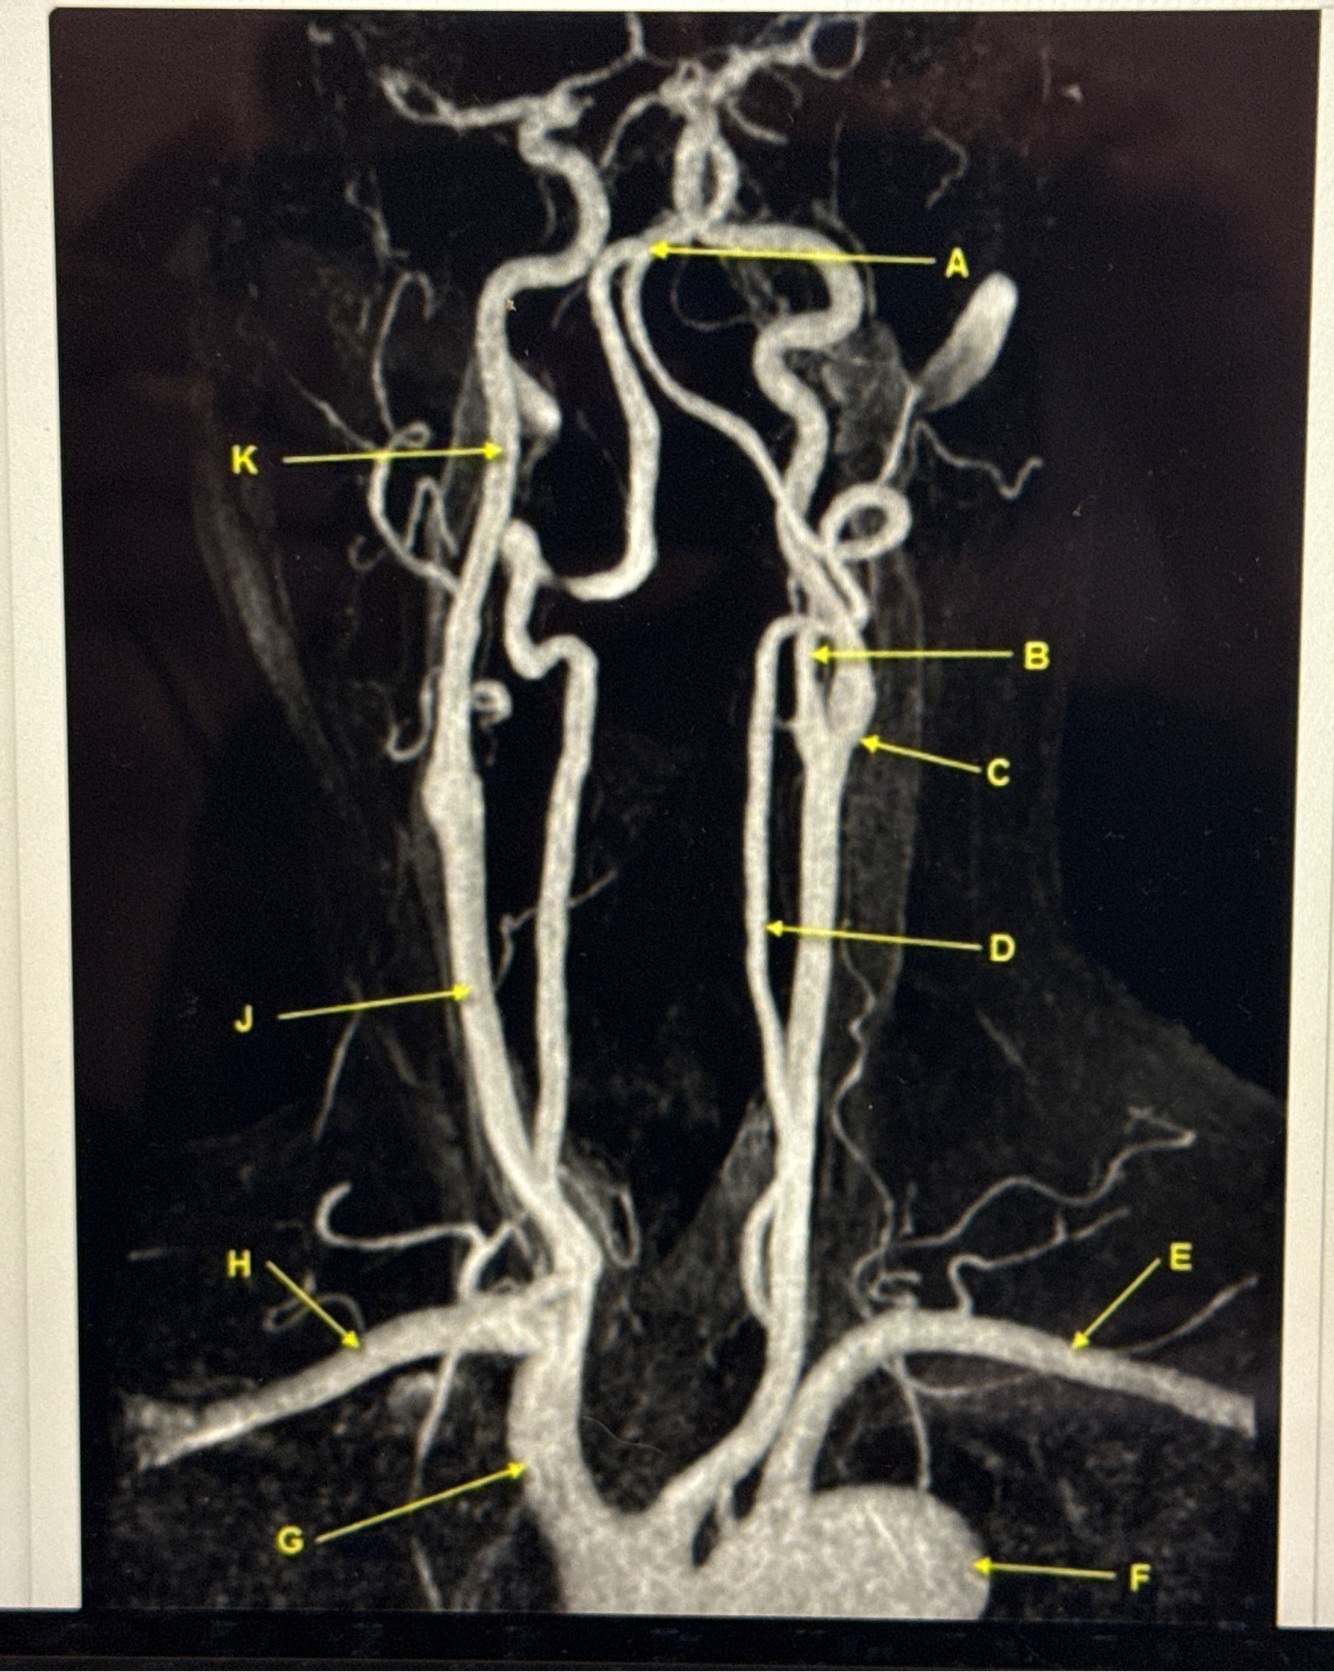

Q

What kind of MR image

A

MRA EXTRACRANIAL CIRCULATION

9

Letter B points to

10

Letter J points to

11

Letter A points to the

12

Letter E points to the

13

Letter K points to the

14

Letter C points to the

16

VertebroBasilar junction

17

Letter B points to the _______ and letter D points to the ______

B. External carotid artery

D. Vertebral artery

18

19

Letter E points to the _____ and letter F points to the _____

E. Left subclavian artery

F. Thoracic aorta

20

Letter G points to the _____ , letter H points to ______ and letter J points to the

G. Brachiocephalic

H. Right subclavian artery

J. Common carotid artery

21

22

Letter K points to the ________,

K. Internal carotid artery